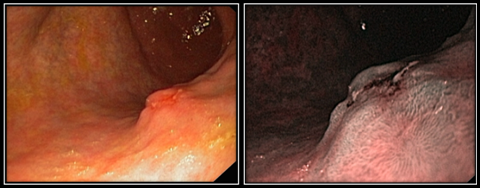

Рис. 1 (а, б). Эндофото. Плосковозвышающаяся форма НЭО желудка

Во всех случаях данная форма НЭО сочеталась с явлениями умеренно выраженной либо выраженной атрофии слизистой оболочки, которые проявлялись в усилении сосудистого рисунка слизистого и подслизистого слоев и истончении слизистого слоя. При осмотре с оптическим увеличением области патологического очага архитектоника слизистой оболочки либо представлена ямочным рисунком соответствующего отдела желудка, где локализуется опухоль, либо соответствует ее гиперпластической перестройке. Последняя определяется удлинением и извитостью ямок слизистой оболочки желудка, увеличением расстояния между ними, а также увеличением ширины и высоты желудочных валиков, при этом сохраняется регулярность ямочного рисунка без формирования участков его деструктуризации (рис. 1а). Изменение архитектоники сосудистого рисунка проявляется в виде появления сети полнокровных извитых сосудов, ограниченной зоной образования, которая более детально визуализируется в режиме NBI. Угловатый рисунок сосудов обусловлен расширением крупных посткапиллярных вен, имеющих звездчатую форму (v. v. stellatae) и локализующихся непосредственно под эпителием слизистой оболочки желудка (рис. 1б).